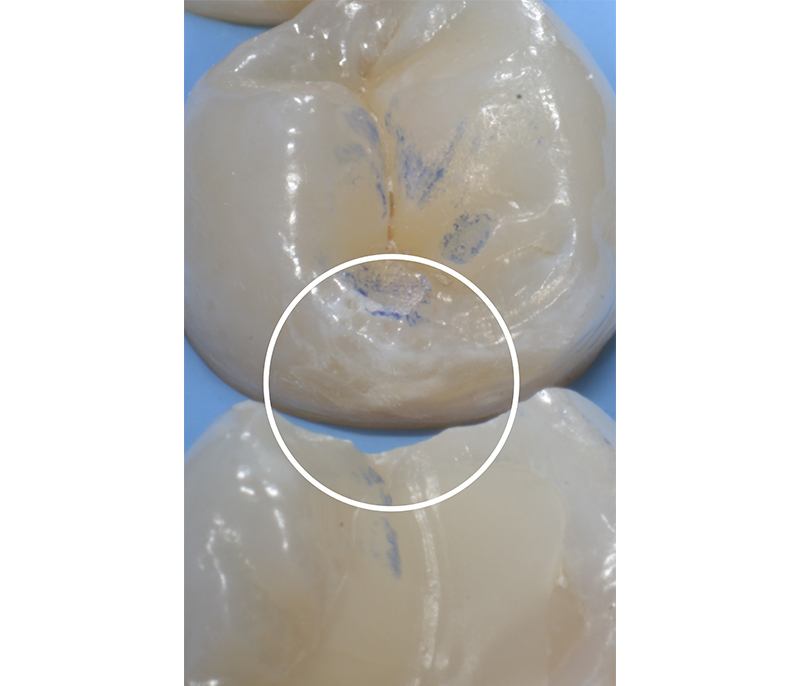

In una paziente di 30 anni, durante un esame radiografico di routine viene rilevata una lesione cariosa interprossimale cavitata sul 36 mesiale ed una lesione cariosa interprossimale non cavitata sul 35 distale coinvolgente radiologicamante la metà interna dello smalto (E2, Fig. 7 e Fig. 8).

In fase di trattamento restaurativo del 36 mesiale, la paziente viene trattata con una singola applicazione di CURODONT™ REPAIR sul 35 distale. Una volta concluso il trattamento, alla paziente vengono fornite le istruzioni di igiene orale di routine e le viene consegnato un tubetto di CURODONT™ PROTECT (Fig. 9). Sei mesi dopo il trattamento, alla visita di follow-up, si osserva radiologicamente la regressione della lesione.

Fig. 7 - Immagine radiografica prima dell’applicazione, lesione cariosa interprossimale cavitata

sul 36 mesiale e non cavitata sul 35 distale.

Fig. 8 - Immagine della lesione prima dell’applicazione di CURODONT™ REPAIR.